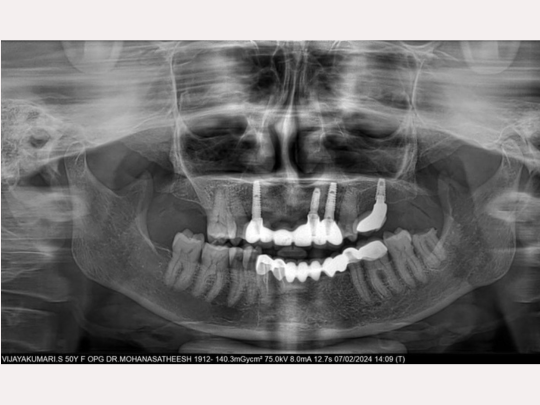

Implant

Before and After